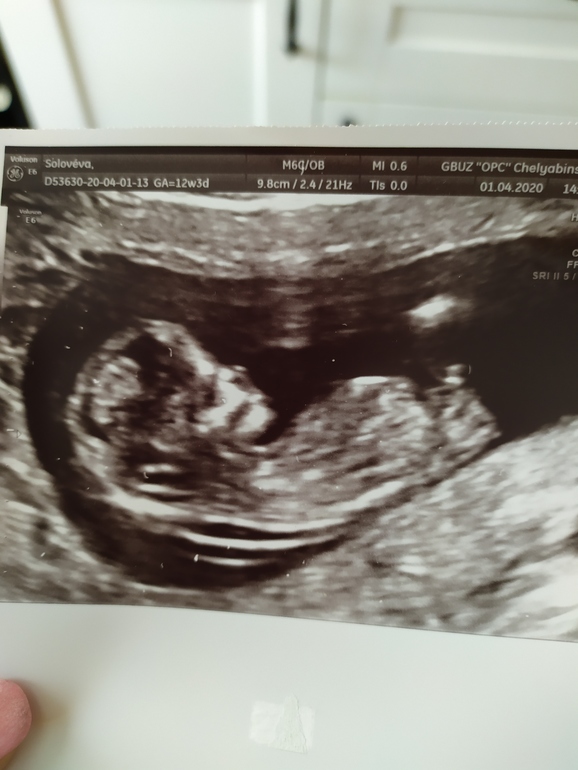

Пол ребенка в 12,5 ндель. А вы видите?

Пол малышаПо результатам первого УЗИ в 12,5 недель у нас мальчик по половому бугорку. В четверг иду на второй скриниг :-) в прошлый раз этот же врач по бугорку нам сына правильно сказала .12,5 ндель. 👇ОБНОВЛЕНИЕ : 19,5 недель -это мальчик👦!)

Мне сказала 99% 😄 мальчик)) просто фотка не очень, вот с сыном там на фотке прям все видно и без сомнения как по книге. Я рада и мальчику и девочке, мне разницы нет вообще.

Ага, фотку специально просила с бугорком... Ну видимо это самый удачный был кадр. ) я вообще ей верю, что мальчик :-)